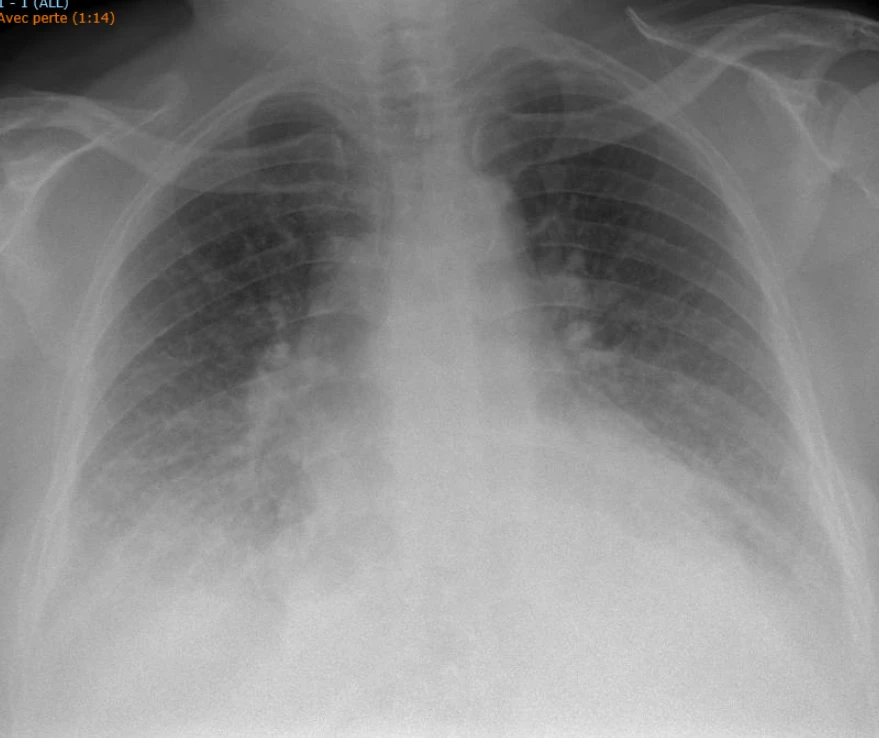

Voici la radiographie du thorax :